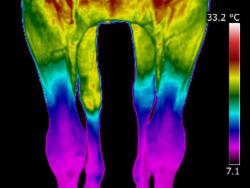

| Nerve injury due to direct trauma or secondary to another injury or disease can affect blood flow and can be visualised with thermal imaging. Rarely interpreted correctly, I have been trained in nerve evaluation and dermatome recognition. Nerve damage is an subject that greatly interests me and thermal imaging is the perfect modality to assess it.

| Interpretation is made more difficult as the horse thermo-regulates, in one, two or more limbs, (image far right). Training and experience is key to correct interpretation.